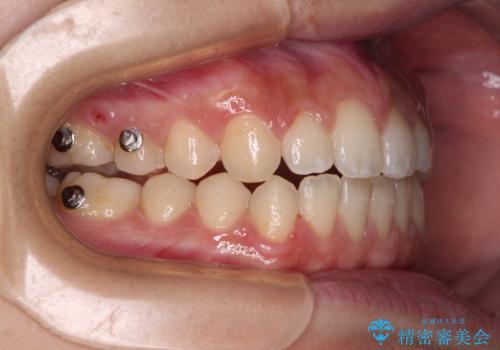

- 矯正装置

- インビザライン

- 治療期間

- 1年10ヶ月

- 治療回数

- 10-30回